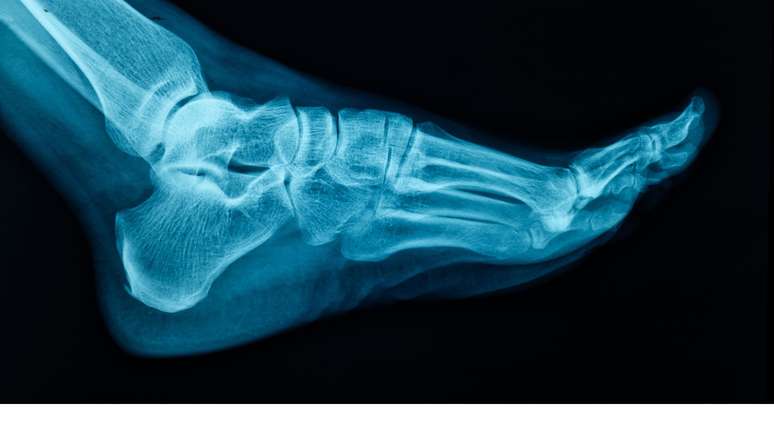

As intervenções cirúrgicas na região do pé são, em sua maioria, motivadas por traumas, desgastes e condições adquiridas, como o joanete e o pé plano

As intervenções cirúrgicas na região do pé são, em sua maioria, motivadas por traumas, desgastes e condições adquiridas, como o joanete e o pé plano. Sanhudo, que também atua no desenvolvimento de dispositivos médicos com a NeoOrtho, destaca que o uso de calçados inadequados é um dos grandes vilões da saúde ortopédica. Escolher sapatos que não oferecem estabilidade e amortecimento pode desencadear dores não apenas nos pés, mas também nas pernas e na coluna. "É fundamental escolher sapatos que ofereçam uma combinação de estabilidade e amortecimento eficaz para absorver o impacto e proporcionar estabilidade durante a marcha", explica o médico. O ajuste deve ser perfeito desde o início para evitar bolhas, calos e insegurança ao caminhar.